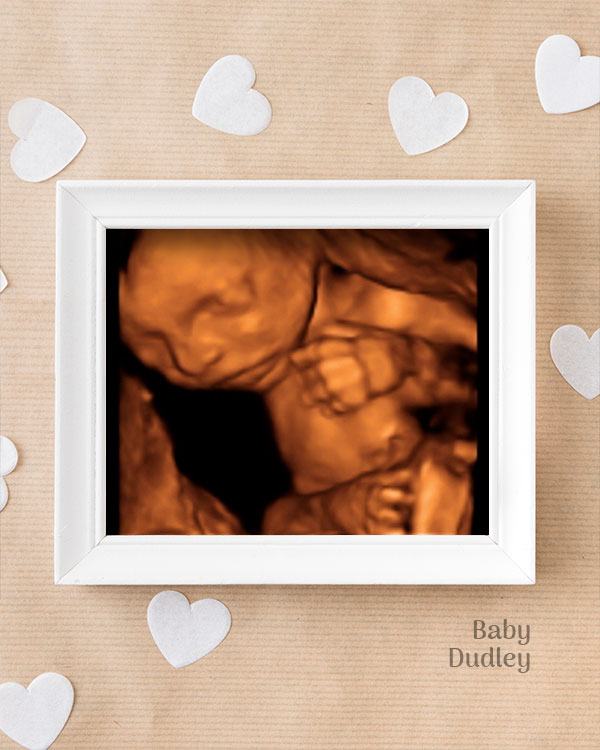

3D / 4D Baby Scan

Mediserv Diagnostics pioneered 4D scanning in the Malabar region. These advanced scans provide realistic images of the baby, allowing detailed evaluation of fetal structures and movements while creating a meaningful bonding experience for parents.